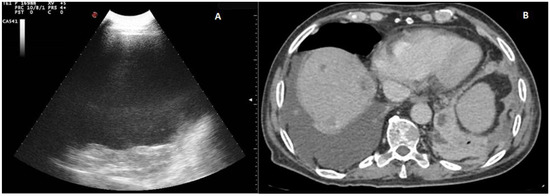

According to the macroscopic appearance, in 54 patients (14.96%) pleural effusion was hemorrhagic, in 297 (82.27%) citrine, and in 10 patients (2.77%) torbid. Based on the composition of the drained fluid, pleural effusions were classified as transudate in 27 patients (7.48%) and exudates in 334 patients (92.52%). On TUS examination, pleural effusions showed an anechoic appearance in 165 patients (45.71%), a heterogeneous ipo-iperechoic appearance (i.e., complex nonseptated) in 174 patients (48.20%), and a homogeneous hyperechoic appearance in 22 patients (6.09%). All the pleural effusion (100.0%) classified as transudates according to Light’s criteria showed an anechoic TUS appearance (Figure 2).

Only the exudative effusions showed a complex nonseptated or a hyperechoic TUS appearance. Considering the pleural effusions classified as exudates, the frequency distribution of the anechoic TUS appearance (n = 138/334, 41.32%) and of the complex nonseptated pattern (n = 174/334, 52.09%) were statistically higher than that of the homogeneous hyperechoic one (22/334, 6.59%), with a p-value < 0.0001. The number of complex nonseptated exudates was statistically higher compared to that of the anechoic ones (p = 0.005) (Figure 3).

Figure 2. (A) TUS scan showing an anechoic effusion with consensual parenchymal atelectasis during thoracentesis with a multifrequency convex probe (3.5 MHz). The tip of the needle is highlighted by a white arrow. (B) The corresponding CT scan shows a smooth thickening of the peribronchovascular interstitium and a bilateral pleural effusion with passive atelectasis of lower lobe in the right lung (black arrow).